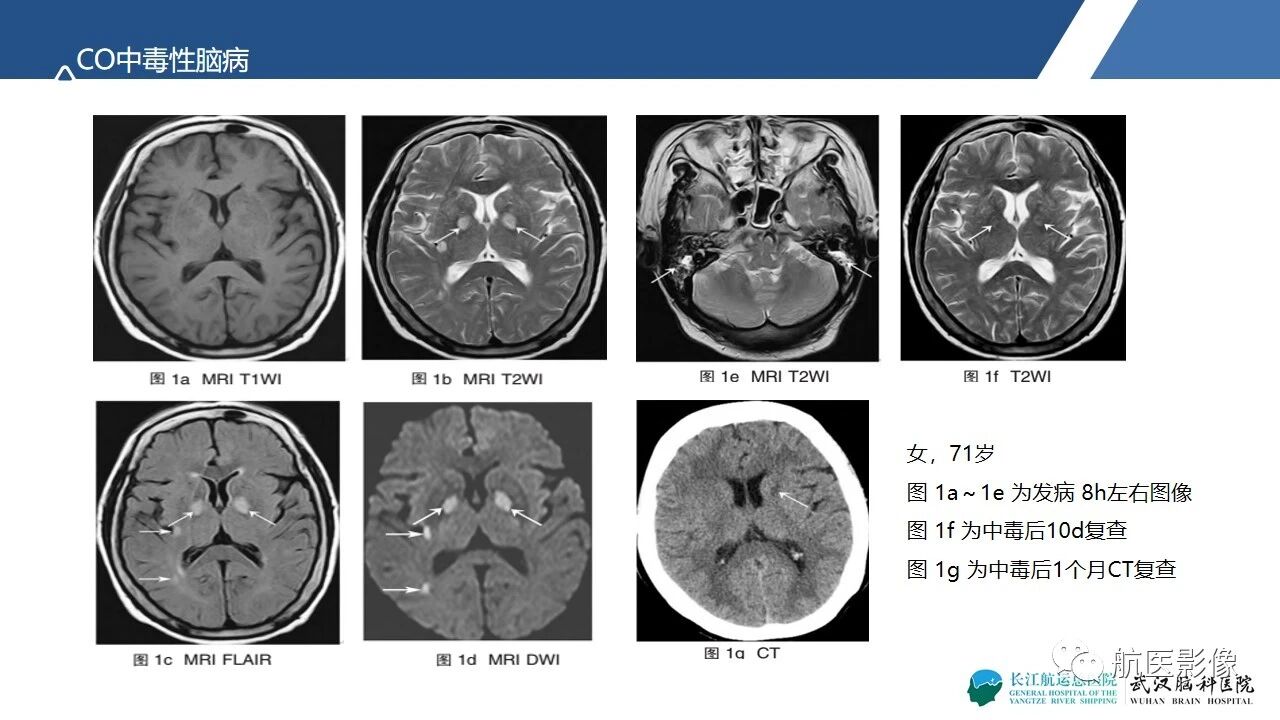

基底节区、丘脑对称性病变影像表现